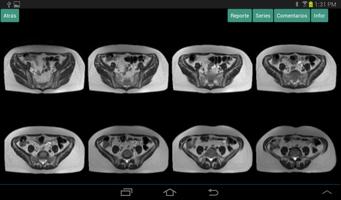

Sebagai pelengkap penggunaan Synapse-PACS, referensi-sinapse ditawarkan, alat yang memungkinkan referensi untuk berkonsultasi dengan studi pasien mereka, melalui koneksi berbagai sumber informasi seperti rumah sakit, pusat interpretasi, laboratorium, dll. Agile dan melalui satu alat visualisasi.

Setelah penelitian berada, gambar dibuka dengan cara yang sederhana, dapat memilih melalui berbagai rangkaian studi dan dari sana menuju masing -masing gambarnya. Ini juga menyajikan laporan interpretasi yang dibuat oleh ahli radiologi, alat untuk memanipulasi gambar dan menyoroti karakteristik gambar, seperti cluster, kecerahan, kontras, rona, dll.